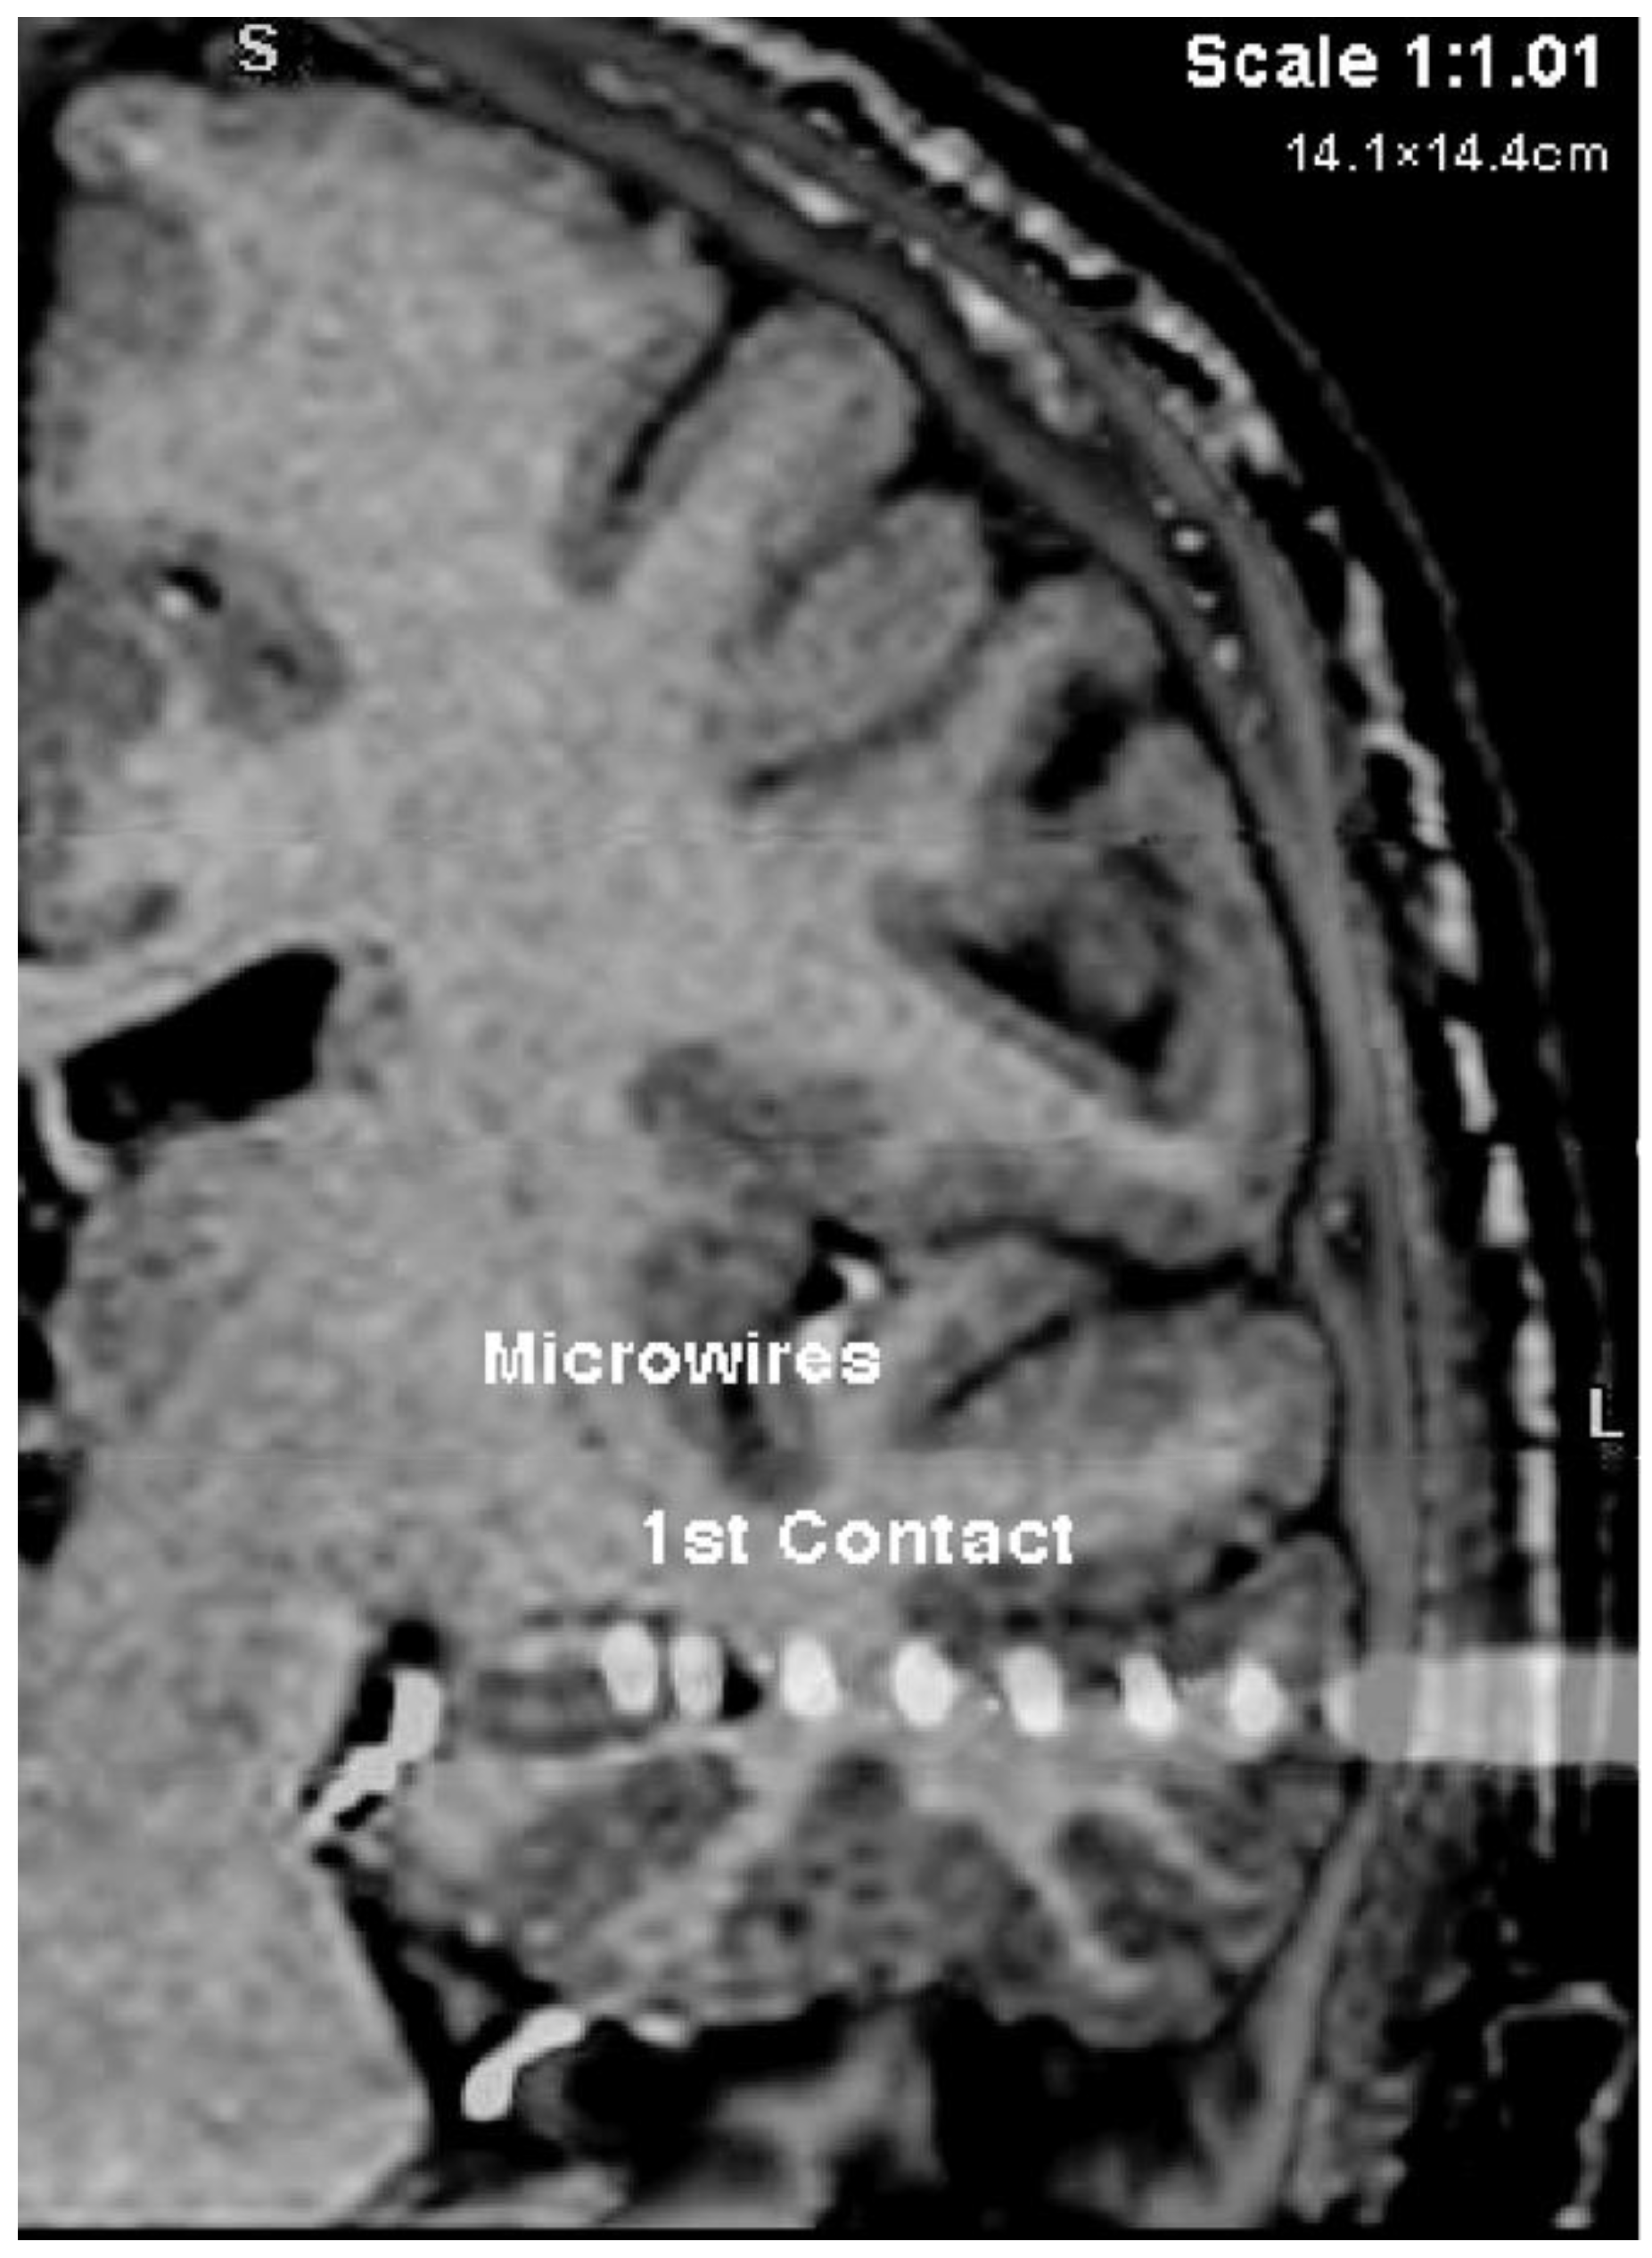

Microwire Bundles and Recording System. Extracellular action potentials corresponding to single-neuron activity were recorded from microwire tips implanted bilaterally along with clinical depth electrodes used to record clinical field potentials [34,35]. The implantation sites were chosen according to clinical criteria, which limits the potential recording sites. For these patients, and per standard clinical practice at the BNI, the sites included the bilateral hippocampus, prefrontal cortex, anterior cingulate cortex, and amygdala. In the hippocampus, the wires were targeted to the midbody of the hippocampus, just behind the head of the hippocampus, opposite the apex of the cerebral peduncle. In the prefrontal cortex, the wires were targeted to the ventromedial prefrontal cortex, below the anterior cingulate gyrus. In the anterior cingulate, the wires were targeted to parts above and behind the genu of the corpus callosum. In the amygdala, the wires were targeted to be in the center of that structure.

Each recording site received a bundle of nine 38 µm-diameter platinum-iridium microwires (California Fine Wire, Grover Beach, CA, USA), implanted stereotactically (Medtronic StealthStation, Minneapolis, MN, USA) using a 1.5-T structural MRI. Each microwire typically had an impedance of 300 kΩ at 1000 Hz. Electrodes were placed through a skull bolt with a custom frame to align the depth electrode along the chosen trajectory. The error in tip placement using this technique is estimated to be ±3 mm based on manual inspection of the pre-operative MRI and post-operative CT and prior work [36,37]. While this technique, lacking co-registration of a post-operative CT with the preoperative targets, cannot guarantee placement within the targeted brain structures, the majority of microwire bundles are estimated to be in the targeted structures. We, therefore, refer to the position of the microwires as within their targeted structures throughout the results presented here; we address this limitation in the General Discussion.

Figure A3. CT scan of the left hemisphere with macroelectrode and microwires implanted in the hippocampus.